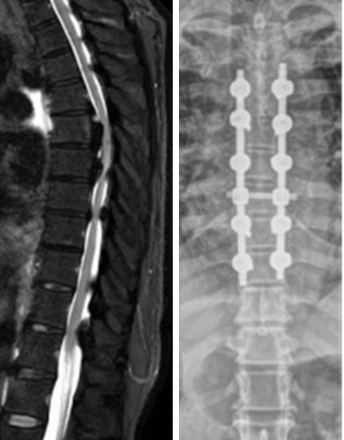

Incidental Spinal Durotomies Noted During Spinal Surgery: Incidence and Management